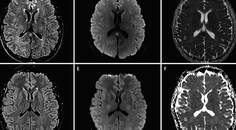

Reversible and Benign Lesions of Splenium of The Corpus Collosum

Dhanashri P. Miskin, MD; Jared Steinklein MDDhanashri P. Miskin, MD; Jared Steinklein MD